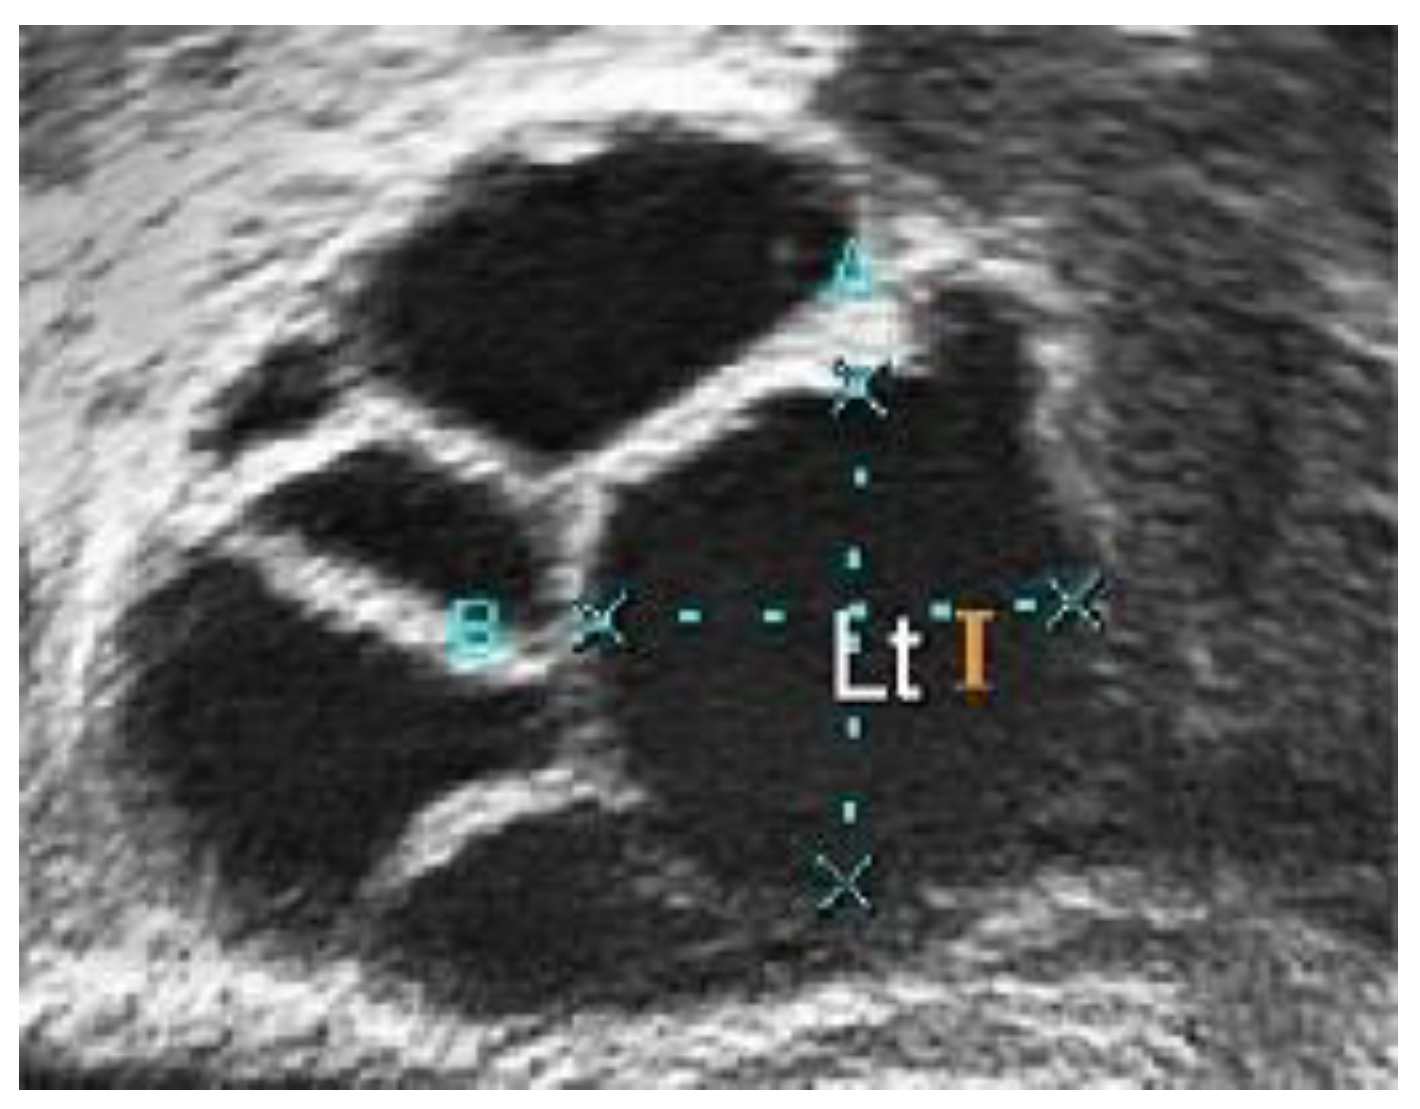

Figure 13 shows another ultrasound image with three different segmentations: manual segmentation, classical Chan–Vese, and the proposed segmentation method. This ultrasound image has better image quality and lesser speckle noise reduction than the others. Figure 13a shows the original ultrasound image. Compared with Figure 12a, the speckle noise disturbances in Figure 13a do not affect the ultrasound. Moreover, Figure 13b shows the binarized follicles marked by a medical practitioner to provide a ground truth image for this study. Figure 13c,d show the difference in segmentation results. The follicles in Figure 13c, segmented using the classical Chan–Vese method, are poorly identified. The follicle boundaries may have been poorly identified during pre-processing, and without using the Otsu thresholding method, the boundary pixels have affected the segmentation results. This poor boundary detection will affect size measurements. The segmented image in Figure 13d is the closest to the manually segmented image. With the help of Otsu thresholding, the pixels have been segregated clearly to show the follicle area.

Figure 13.

Comparison of different segmentation methods. (a) Original ultrasound image; (b) manual segmentation; (c) classical Chan–Vese method; and (d) Otsu thresholding and the Chan–Vese method.

A comparison of the ground truth and segmented images is shown in Figure 12 and Figure 13. The images obtained using classical Chan–Vese method and the proposed method in Figure 12c,d and Figure 13c,d show that some false follicles were detected, because the pixel intensities in the particular area mimicked the intensities of PCOS follicles. The quantitative values of image segmentation were calculated in order to compare the effectiveness of the methods.